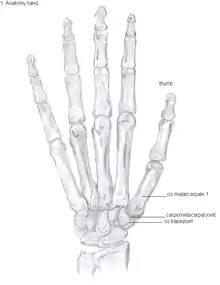

Anatomy

The CMC1 joint is a synovial joint between the trapezium bone of the wrist and the metacarpal bone at the base of the thumb. This joint is a so-called saddle joint (articulatio sellaris), unlike the CMC joints of the other four fingers which are ellipsoid joints.[16] This means that the surfaces of the CMC1 joint are both concave and convex.

This high mobility is due to the little intrinsic osseous stability of the joint. This causes the CMC1 joint to be more unstable compared to the CMC joints of the other fingers.[18] Because of this instability, the joint is more susceptible to be damaged.[12] To remain stable the CMC1 joint has to rely on the surrounding ligaments for support. These ligaments provide the ability to subject high pressure loads, particularly during pinch and grasp manoeuvres.[19]

16 ligaments surrounding the CMC1 joint are identified, which give strength and stability to the joint. Of these ligaments, the deep anterior oblique ligament, also known as the palmar beak ligament, is considered to be the most important stabilizing ligament.[20]